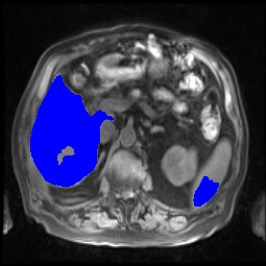

Integrating high-level semantically correlated contents and low-level anatomical features is of central importance in medical image segmentation. Towards this end, recent deep learning-based medical segmentation methods have shown great promise in better modeling such information. However, convolution operators for medical segmentation typically operate on regular grids, which inherently blur the high-frequency regions, i.e., boundary regions. In this work, we propose MORSE, a generic implicit neural rendering framework designed at an anatomical level to assist learning in medical image segmentation. Our method is motivated by the fact that implicit neural representation has been shown to be more effective in fitting complex signals and solving computer graphics problems than discrete grid-based representation. The core of our approach is to formulate medical image segmentation as a rendering problem in an end-to-end manner. Specifically, we continuously align the coarse segmentation prediction with the ambiguous coordinate-based point representations and aggregate these features to adaptively refine the boundary region. To parallelly optimize multi-scale pixel-level features, we leverage the idea from Mixture-of-Expert (MoE) to design and train our MORSE with a stochastic gating mechanism. Our experiments demonstrate that MORSE can work well with different medical segmentation backbones, consistently achieving competitive performance improvements in both 2D and 3D supervised medical segmentation methods. We also theoretically analyze the superiority of MORSE.

翻译:在医学图像分割中,整合高级语义相关的内容和低级解剖特征对于模拟这些信息非常重要。近期基于深度学习的医学分割方法已经显示出很有前景,可以更好地建模这些信息。然而,医学分割的卷积运算符通常在正则化网格上运作,这在本质上模糊了高频区域,即边界区域。我们在这项工作中提出了 MORSE,这是一个设计在解剖学水平上的通用隐式神经渲染框架,用于协助医学图像分割的学习。我们的方法的动机在于隐式神经表示已经被证明比离散化网格表示更有效地拟合复杂信号和解决计算机图形问题。我们方法的核心是将医学图像分割连续地对准粗糙的分割预测和模棱两可的基于坐标的点表示,并聚合这些特征来自适应地精细化边界区域。为了并行地优化多尺度像素级特征,我们借鉴了 Mixture-of-Expert (MoE) 的思想设计和训练我们的MORSE,使用随机门控机制。我们的实验表明MORSE可以很好地与不同的医学分割后骨干结合在一起,始终在2D和3D监督医学分割方法中实现了有竞争力的性能改进。我们还从理论上分析了MORSE的优越性。